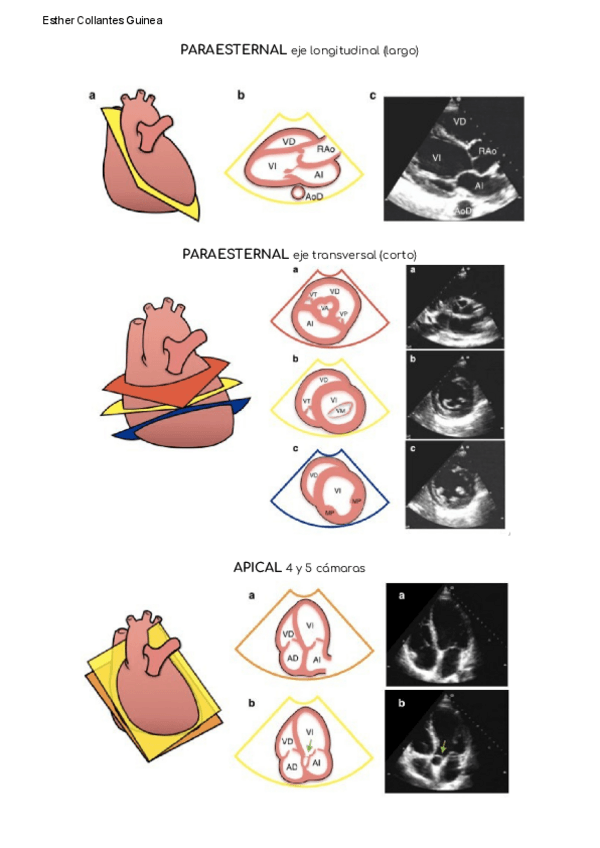

He publicado nuevos apuntes de 1º Fisiología Básica: ECOCARDIOGRAMA.pdf